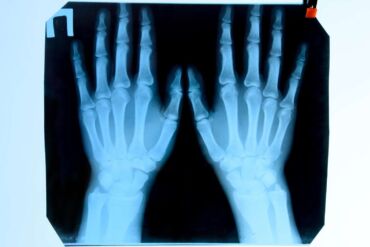

Röntgenové lúče prechádzajú telom, sú absorbované v rôznych množstvách tkanivami v závislosti od ich hustoty (denzity). Najlepšie bývajú zobrazené kostné štruktúry.

Hustejšie materiály, ako kosti či kovy, sú zobrazené na röntgenových snímkach biele. Na druhej strane, vzduch, napríklad v pľúcach, zobrazuje sa čiernou farbou. Tuk a svaly sa zobrazujú ako odtiene šedej.

Slávna sa stala röntgenová snímka ruky jeho manželky, z roku 1895.

Pri snímkach (röntgenograme) je možné vidieť kovové materiály, ako napríklad implantáty kĺbov (tzv. endoprotézy). Aj preto sa stal röntgen výborným pomocníkom lekára.